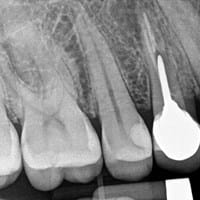

Extracción o re endodoncia, que es lo mejor? RX adjuntos

Junto con saludar, Les comento que hace algunos años, me hicieron una endodoncia en la pieza 14, que resulto con una quebradura de una de las puntas del diente, posteriormente se me reparó con una incrustación, la cual falló y finalmente otro...